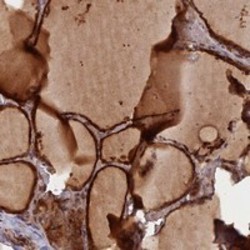

- Immunohistochemical staining of human thyroid gland with GMCL1 polyclonal antibody (Cat # PAB23562) shows strong cytoplasmic positivity in glandular cells at 1:50-1:200 dilution.

- Immunohistochemistry (Formalin/PFA-fixed paraffin-embedded sections)